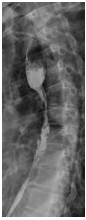

3 Months After Carbon Ion

Before Photon Radiotherapy Before Carbon Ion Radiotherapy After Carbon Ion Radiotherapy